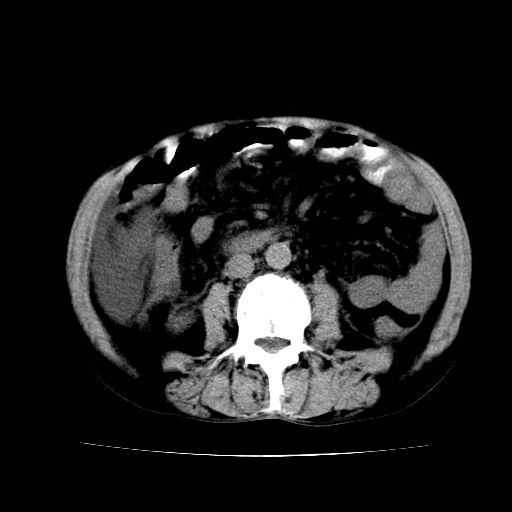

男,55岁,发现“肝硬化”5年,现腰疼、腹胀10余日,巩膜黄染、腹稍胀,肝肋下3指,质硬无压疼,移动性+,血生化:总胆、直胆、间胆均升高。

肝硬化,脾大,腹水

脂肪肝

肝内多发低密度灶(建议增强扫描除外肝癌)

肝脾肿大,脂肪肝,腹水。建议增强除外肝癌。

腹部病变,ct平扫如同隔靴搔痒,建议增强后上传资料。